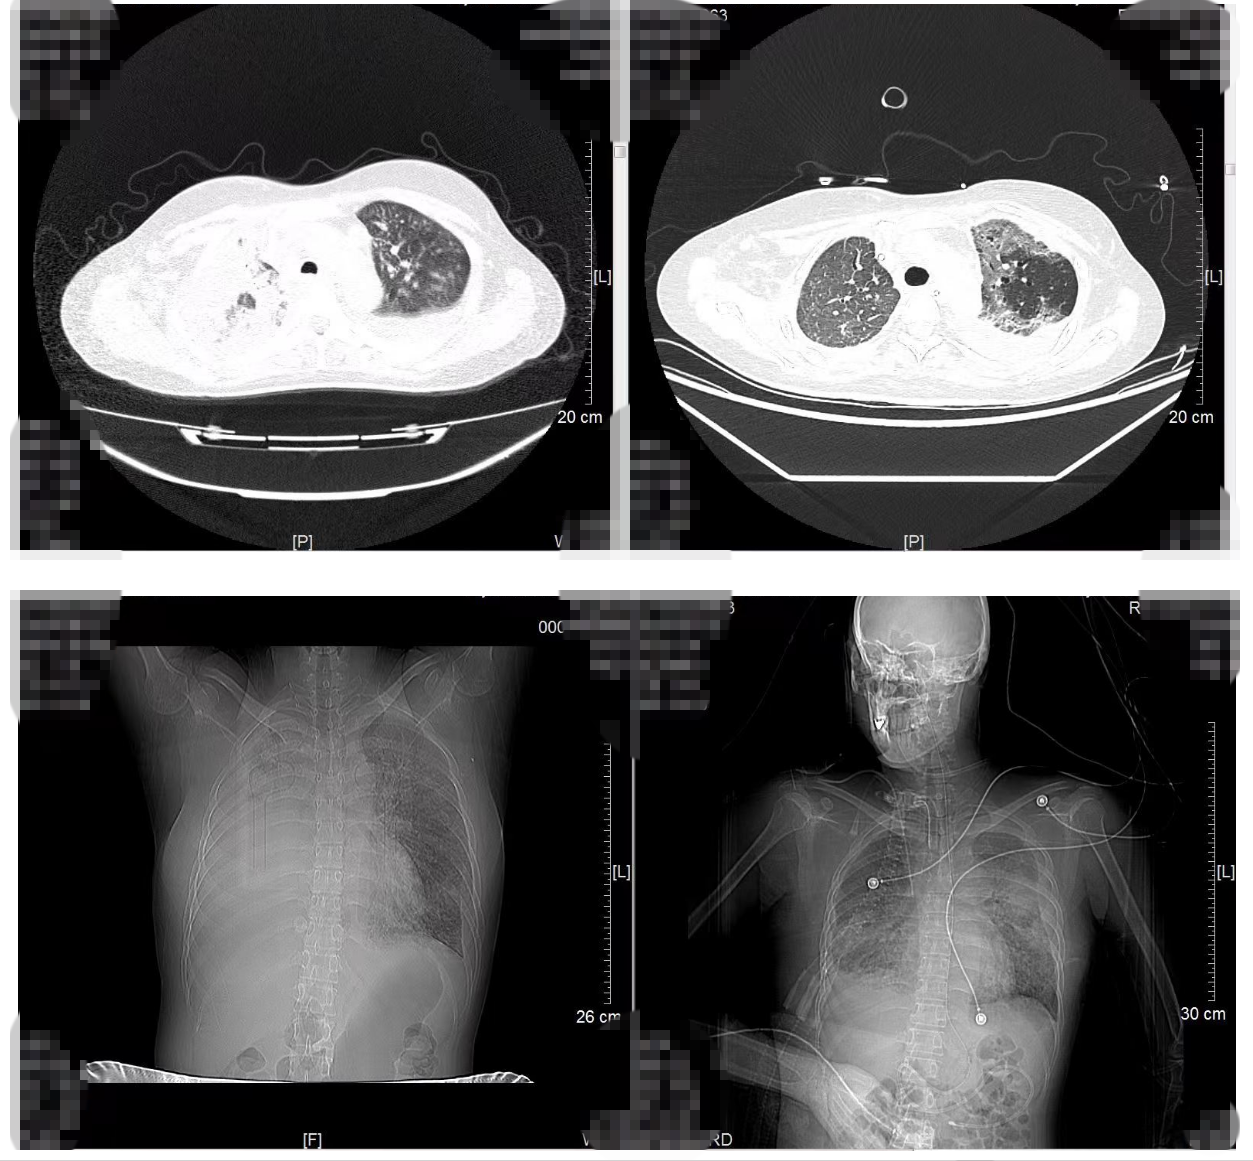

生命支持下的抗肿瘤治疗并非易事。治疗期间章女士出现多脏器功能不全及凝血功能异常,叶勇主任团队为其进行脏器功能保护治疗以保证抗肿瘤治疗顺利进行。经过一个月的靶向治疗,让患者的呼吸功能逐步恢复,部分肿瘤较前退缩。患者恢复清醒,病情好转,已转至普通病房。

治疗前后肺部影像学对比:左图,治疗前;右图,治疗后